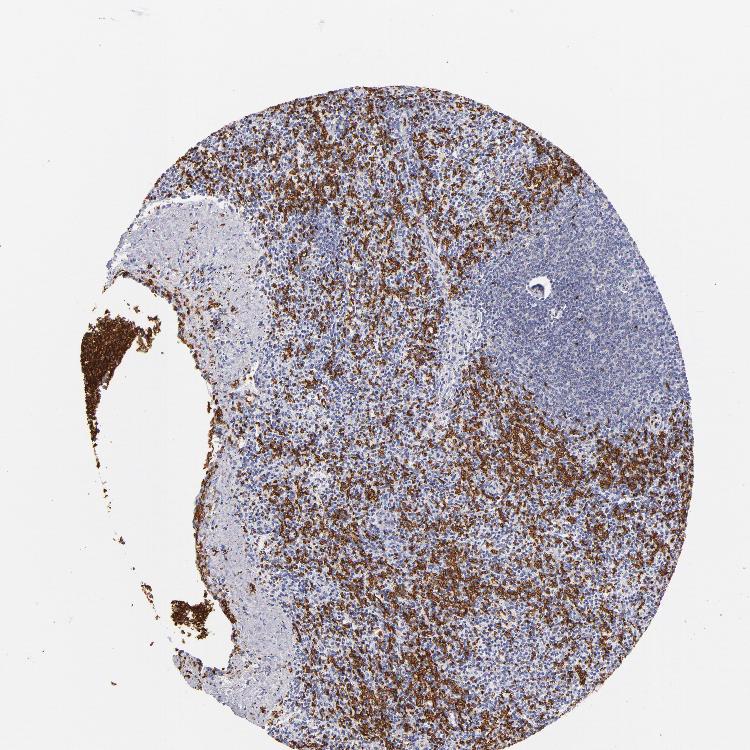

SPLEEN - Antibody stainingi

Antibody staining in the annotated cell types in the current human tissue is reported as not detected, low, medium, or high, based on conventional immunohistochemistry profiling in selected tissues. This score is based on the combination of the staining intensity and fraction of stained cells.

Each image is clickable and will lead to virtual microscopy that enables deeper exploration of all samples and also displays staining intensity scores, fraction scores and subcellular localization as well as patient and tissue information for each sample.

Antibody HPA014811Antibody CAB002658

Cells in red pulp LowNot detected

Cells in white pulp Not detectedNot detected